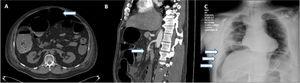

Ocho pacientes fueron diagnosticados por medio de TC abdominal, 6 de ellos presentaron signos de neumoperitoneo, lo cual fue indicio de perforación intestinal (fig. 1A). Un paciente presentó trombosis de la arteria mesentérica superior (fig. 1B), sin aire libre o signos de perforación. El otro paciente presentó una fístula enterocutánea, conectando la piel con un sitio de yeyunostomía previa (14 años), de acuerdo a lo observado por medio de TC. Dos pacientes fueron diagnosticados por medio de radiografía torácica que reveló aire subdiafragmático consistente con perforación intestinal (fig. 1C). Uno de los pacientes antes mencionados (H, 74) murió 7h después del diagnóstico, durante la resucitación preoperatoria e intentos de estabilización hemodinámica como preparación para cirugía de emergencia. En los demás pacientes se realizó laparotomía.